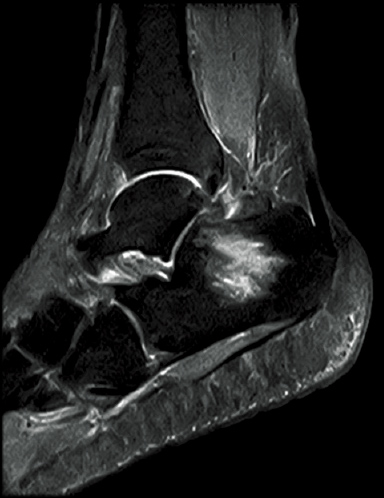

FatSep-T2*WI